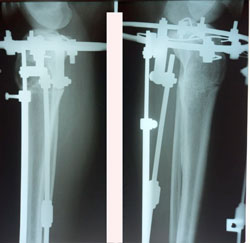

Исходник 40 лет.

Дата операции - 18.09.2020

Дата снятия аппаратов - 16.01.2021